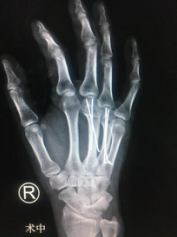

于是,刘先生辗转来到我院,正逢手外二熊祖国医生坐门诊。熊医生看完片子,告诉他可以微创手术,而且术后手功能基本恢复正常。刘先生一听很高兴,希望能尽快安排手术。熊医生为其采用的治疗方案为闭合复位经皮微创克氏针内固定,既能很好地固定骨折,还不留疤痕,早期通过功能锻炼,达到恢复功能。熊医生和吴衡医生团队很快做完了手术,术后第二天刘先生就出院了。

术中

出院时,针对他的伤情,专门制定了刘先生复诊时间及根据恢复情况循序渐进进行指导功能锻炼,刘先生的手终于恢复正常了,骨头长好了,钉子也取出来了。刘先生看到自己现在的手感慨万千,一方面非常后悔一时冲动伤害了自己,另一方面又感觉很幸运,遇到了两位好医生,不然自己真得可能会因此放弃热爱的事业。

内固定取出后

熊医生介绍,刘先生术前右手不能握拳,伸不直,伸屈都有影响,术后功能基本恢复正常。